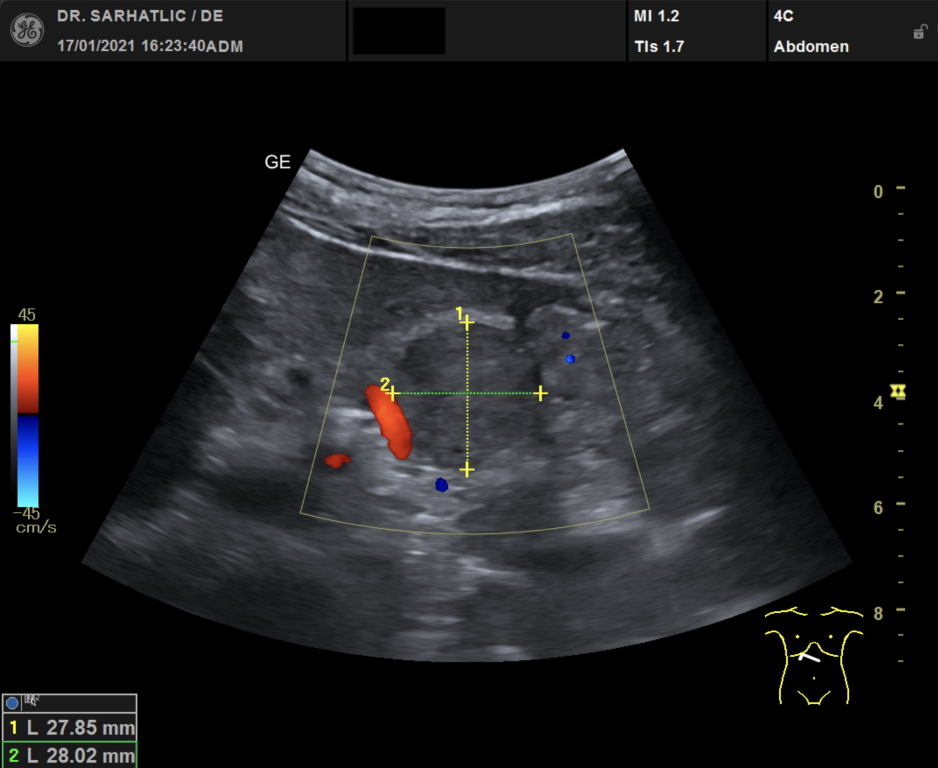

- Ultraschall aller inneren Organe (z. B. Leber, Bauchspeicheldrüse, Nieren, Prostata, Schilddrüse)

- Ultraschall der Gefäße (z. B. Halsschlagadern)